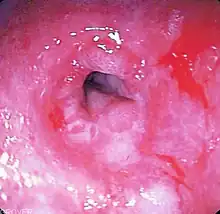

Diffuse scleroderma can affect any part of the gastrointestinal tract.[10] The most common manifestation in the esophagus is reflux esophagitis, which may be complicated by esophageal strictures or benign narrowing of the esophagus.[11] This is best initially treated with proton pump inhibitors for acid suppression,[12] but may require bougie dilatation in the case of stricture.[10]

Scleroderma can decrease motility anywhere in the gastrointestinal tract.[10] The most common source of decreased motility is the esophagus and the lower esophageal sphincter, leading to dysphagia and chest pain. As scleroderma progresses, esophageal involvement from abnormalities in decreased motility may worsen due to progressive fibrosis (scarring). If this is left untreated, acid from the stomach can back up into the esophagus, causing esophagitis and gastroesophageal reflux disease. Further scarring from acid damage to the lower esophagus many times leads to the development of fibrotic narrowing, also known as strictures, which can be treated by dilatation.